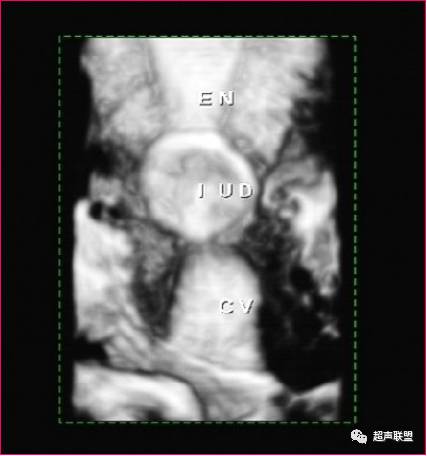

IUD合并妊娠

在子宫内显示妊娠囊与IUD的回声同时存在,可诊断为IUD合并宫内妊娠(带器妊娠)。超声诊断带器妊娠的价值在于能清晰的显示子宫、IUD和妊娠囊,以及三者的关系。

声像图特征:

1、子宫增大,增大的径值与孕周成正比。

2、早期妊娠时,在子宫腔内显示完整的妊娠囊,随妊娠周数的增加,囊内可见到胎芽、原始心管搏动及胎动。在妊娠囊的下方、侧方、上方或接近子宫颈口处,显示强回声的IUD,由于妊娠囊暗区的衬托,IUD回声显示格外清楚。